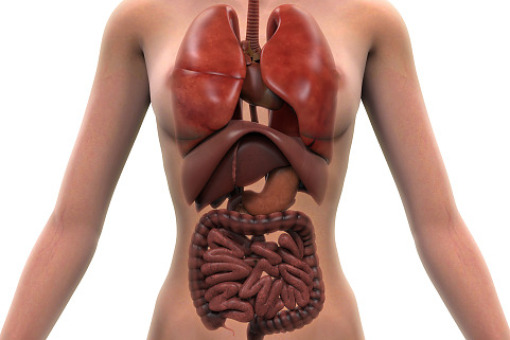

IgG4-RD jest rzadką, przewlekłą chorobą autoimmunologiczną, która powoduje zwłóknienie i stan zapalny w jednym lub wielu narządach. Choroba dotyka zwykle osoby w wieku 40–60 lat. Objawy mogą wystąpić nagle i się nasilać, nieleczone mogą prowadzić do nieodwracalnego uszkodzenia i dysfunkcji narządów.